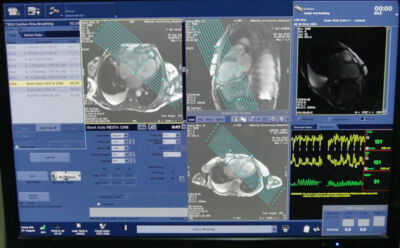

Nachdem die Funktionsfähigkeit der kardinalen Soft- und Hardware des Kernspintomografie-Gerätes im Ader Hospital im März 2019 vom Kardiologen Dr. Christian Leuner festgestellt worden war, wurde vereinbart, bei seinem nächsten Besuch mithilfe eines auf dem Gebiet der kardiologischen Kernspinuntersuchungen spezialisierten Medizinisch radiologischen Assistenten einen Workshop mit dem örtlichen Stammpersonal durchzuführen, und erste äthiopische Patienten zu untersuchen. Dies, um die Kardiologen in der Befundung und die örtlichen radiologischen Techniker in der Erstellung der Bilder zu schulen.

Die Leitung der Radiologie und MRT Abteilung im Ayder Hospital sowie die dortigen Radiologie-Techniker zeigten sich sehr interessiert daran die Möglichkeiten ihres Kernspintomografen zu erweitern. Vonseiten der Kardiologen besteht unverändert ein großes Interesse an dieser Methode der kardinalen Diagnostik, die weltweit immer größere Bedeutung erlangt. Wegen des großen Bedarfs an Kernspinuntersuchungen des Schädels wurde der Workshop am Ende der regulären Arbeitszeit und darüber hinaus durchgeführt.

Mit der Bereitschaft von dem Bielefelder Medizinisch radiologischen Assistenten Simon Hamza für drei Wochen mit nach Mekelle zu kommen, war die Grundlage für eine erfolgreiche Tätigkeit gelegt. Er hat über zahlreiche Jahre im Klinikum Bielefeld im täglichen Betrieb Kardio-MRT Untersuchungen durchgeführt. Begünstigt durch freie Zeit als Ruheständler hat sich Dr. Christian Leuner in einer Kombination von ausgiebigem Lehrbuchstudium und mehrwöchiger praktischer Arbeit in der Abteilung für Kardiale Kernspintomografie unter Anleitung von dem Kardiologen Dr. Jens Reinhard im Klinikum Bielefeld auf den Basis-Workshop im Ayder Hospital vorbereitet.

So gerüstet hat er einführende Vorlesungen in die Methode im Ayder Hospital gehalten und die Basisauswertungen mit vor Ort nur unvollständiger Auswertesoftware mit dem in Deutschland kardiologisch mit ausgebildeten Kardiologen Dr. Samuel Berhane begonnen.

Nach mehreren Tagen des experimentieren gelang es schließlich einige auswertbaren Untersuchungen zu erstellen, die Grundlage für die ersten Schulungseinheiten zur medizinischen Beurteilung der Ergebnisse für die in ihrer freien Zeit naturgemäß sehr eingeschränkten äthiopischen Kardiologen waren.

Gemeinsam mit dem Kardiologen im Ruhestand Dr. Christian Leuner aus Bielefeld sind wir mit dem Ziel zu dem Ayder Comprehensive Specialized Hospital der Mekelle University gefahren, um an dem dort vorhandenen 3 Tesla Kernspintomografen kardiale Kernspintomografie einzuführen bzw. durchzuführen. Die Reise wurde finanziert vom Verein Etiopia-Witten e.V. und der Universität Mekelle.

Schon zu Beginn durfte ich fünf fleißige und engagierte Radiographer kennenlernen, von denen am liebsten jeder als Erster eingewiesen werden wollte. Dieses Verhalten ist zwar lobenswert, jedoch haben wir in Rücksprache mit allen Beteiligten zwei Radiographer bestimmen müssen, damit wir schnell Erfolge erzielen können. Dennoch waren alle Beteiligten hoch interessiert und wollten über die Schultern der Verantwortlichen gucken. Nach Überwindung der ersten Nervosität auf allen Seiten haben wir versucht, schnell erste kardiale Untersuchungen durchzuführen, welche anfänglich schwerer als gedacht waren. Die erste Problematik bestand darin, dass aufgrund des hohen Bedarfs an Bildgebung des Kopfes und der Wirbelsäule wenig Zeit zur Verfügung stand, obwohl im Voraus mehrfach unsere Vorhaben angekündigt wurden. Trotz dessen haben wir mit allen Beteiligten schnell eine Lösung erarbeiten können. Es bestand sogar eine große Bereitschaft der Radiographer extra am Nachmittag, ins Haus zu kommen, um Untersuchungen am Patienten von zwei bis vier Stunden durchzuführen und alle wichtigen Techniken zu erproben, anzuwenden und zu vertiefen. Diese Regelung hatte zum einen den Vorteil, dass ich mir vormittags einen Überblick über den Routinebetrieb der Radiologie verschaffen konnte, um diese Fähigkeiten der technischen Assistenten einzuschätzen und auf unser Vorhaben übertragen zu können. Darüber hinaus nutzten wir die Vormittage, um das weitere Vorgehen zu planen, das Handbuch zu gestalten und die vergangenen Tage zu evaluieren.

Folglich haben wir gemeinsam die Grundbasis geschaffen um erste Herzdiagnostiken durchführen zu können. Es wäre sicher sinnvoll nach einer gewissen Zeiteinheit dies zu evaluieren und weitere technische Möglichkeiten auszuarbeiten, um tiefgehende Diagnostiken anbieten zu können.

Nach längeren Vorbereitungen ist es März 2019 dem Kardiologen Dr. Christian Leuner mit dem äthiopischen Medizin-Ingenieur Fehissa Mehari von der Firma Inifinity-et aus Addis Abeba und den Röntgentechnikern des Ayder Universitätshospitals in Mekelle - Nordäthiopien, erste Darstellungen des Herzens mit dortigen modernen 3Tesla Kernspintomografen (MRT) zu erstellen. Die Schulungen der Techniker und Kardiologen im Ayder Hospital durch von Spezialisten von Etiopia-Witten ist nun möglich.